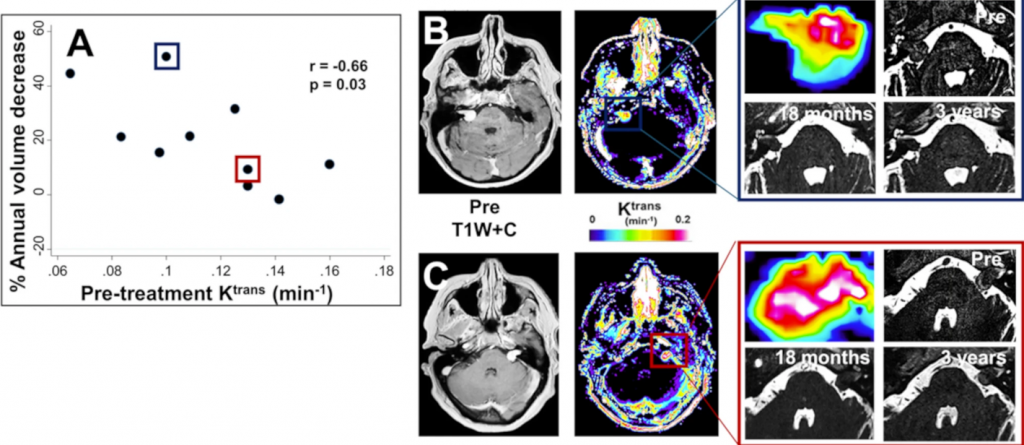

This funding awarded to Daniel and study co-investigators Dr Kaloh Li, Dr Xiaoping Zhu, Professor Alan Jackson and Mr David Coope will support the first steps in the transformation of the DCE-MRI analysis software – currently used in research settings – into a cloud-based clinical decision support tool. The new platform could help clinicians globally not only predict vestibular schwannoma (VS) growth but also analyse imaging data from patients with other brain tumours.

This grant continues research from earlier studies. Daniel’s paper, published earlier this year, is available here: Emerging strategies for the prediction of behaviour, growth, and treatment response in vestibular schwannoma